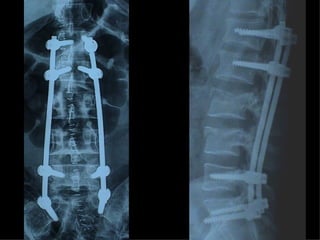

Fratture della colonna vetebrale

Tc pre op

frattura

TC RMN

Rx post

Timing chirurgico 1° GIORNO :- intervento salvavita - “Damage control” - trattamento chirurgico  primario differito 2°-3° GIORNO :  soltanto un “second  look”

5°-10° GIORNO :  “window of  opportunity”  per un intervento  definitivo 10°- 20° GIORNO : NESSUN TRATTAMENTO CHIRURGICO Dal 21° GIORNO : intervento chirurgico secondario - ricostruttivo